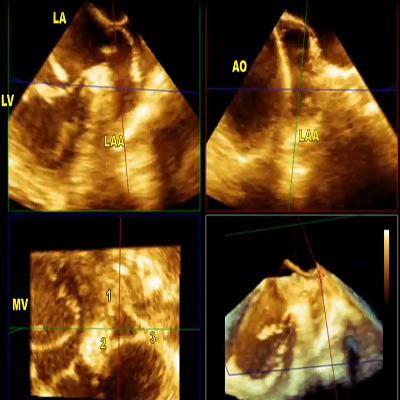

3D TEE zoom mode acquisition of the mitral valve from left atrial perspective

|

2 MB

3D TEE: narrow mitral orifice

|

212 KB

3D TEE: narrow mitral orifice

|

436 KB

3D TEE: narrow mitral orifice

|

169 KB